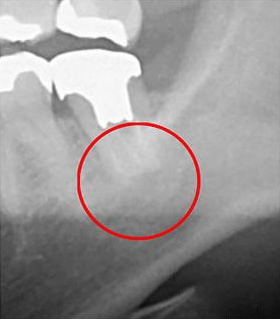

次の画像は、同じ歯をCTとレントゲンで撮影したものの比較です。

左がCT、右がレントゲンとなります。

CT画像(左)では黒い影が見えますが、レントゲン画像(右)にはその影がありません。この黒い影は、歯の根の炎症です。つまり、レントゲンだけで検査していたら、この炎症は見逃されてしまうということです。

CTを使用することで、初期の炎症も見逃すことなく、適切な診断が可能になります。